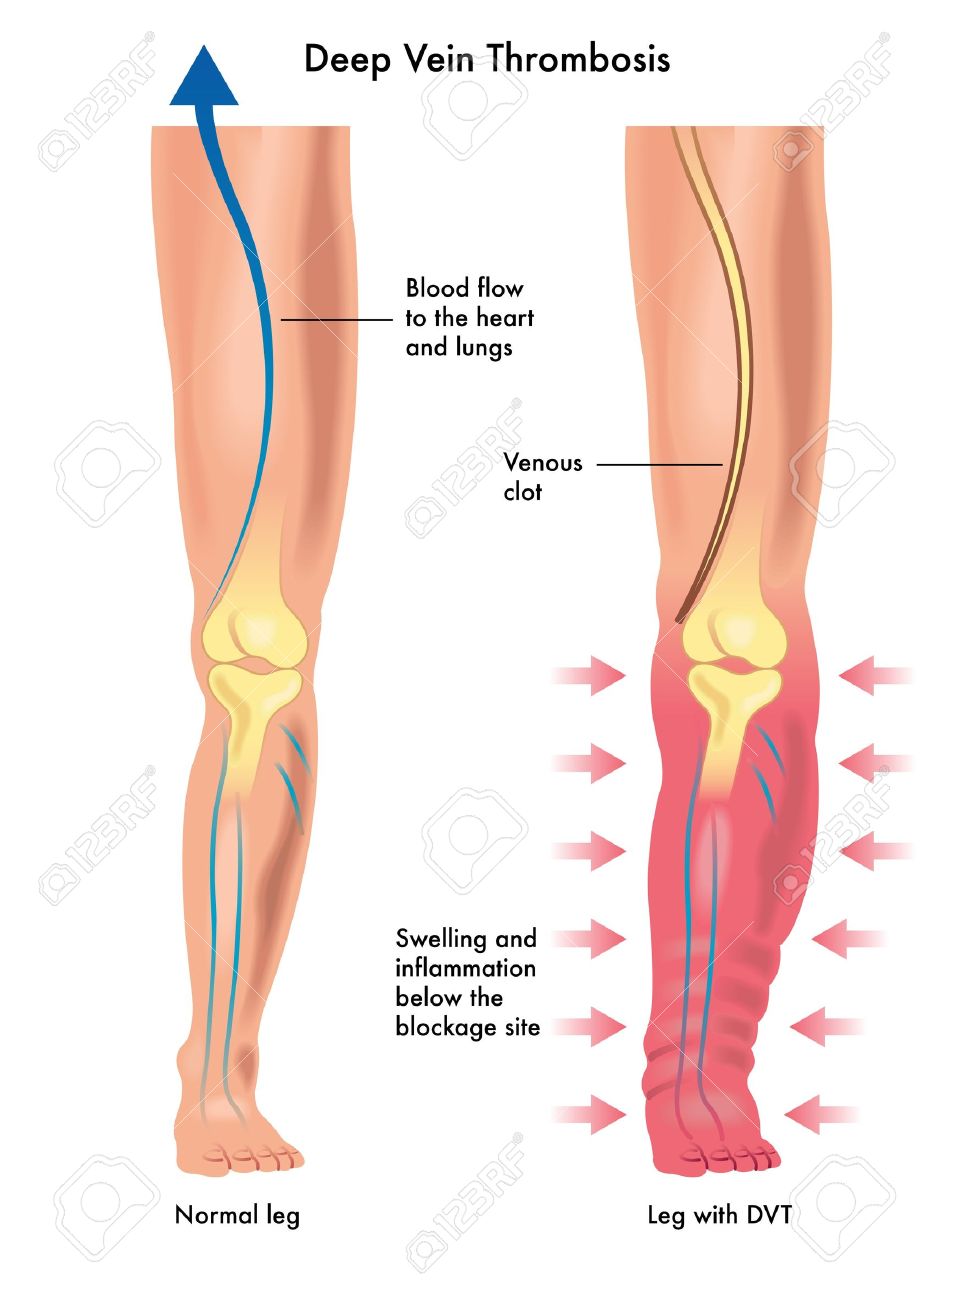

上皇后さまが発症された深部静脈血栓症について解説します下肢静脈瘤の原因・症状・治療方法・予防方法などを専門医が解説。

脚領域における深部静脈血栓症の医学的図。のイラスト素材・ベクター Image 98030310。

深部静脈血栓症 DVT の病態と予防見て!わかる!病態生理と看護 花子のまとめノート。

静脈血栓塞栓症ではどのような症状がありますか? 静脈血栓塞栓症。

深部静脈血栓症、血栓症。塞栓。正常静脈と静脈瘤の構造。イラストは私が作成しました写真素材1443942500Shutterstock。